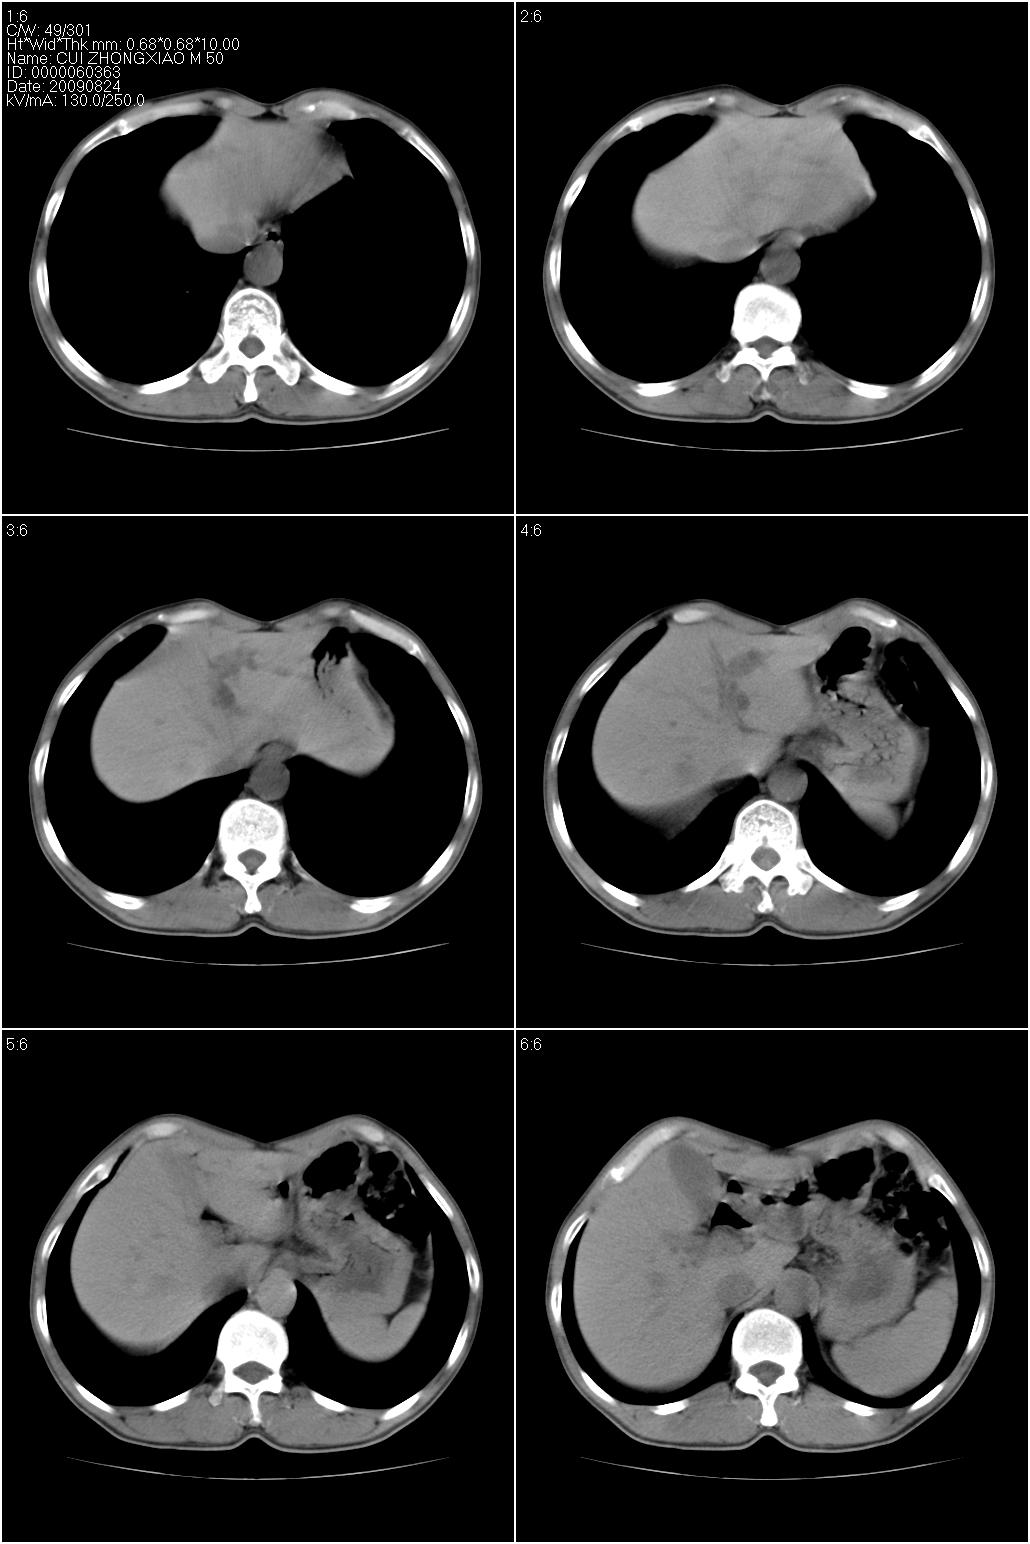

标题: CT21851:男性,50岁。间断性咳嗽半年。 [打印本页]

标题: CT21851:男性,50岁。间断性咳嗽半年。

磨玻璃样改变(左肺及右肺上叶前段),边缘模糊,考虑炎症,建议严格抗炎治疗后复查除外肺泡蛋白沉积症或肺泡出血(病人有咯血吗) 肺泡癌.

肝左叶肝内胆管扩张,进一步检查.